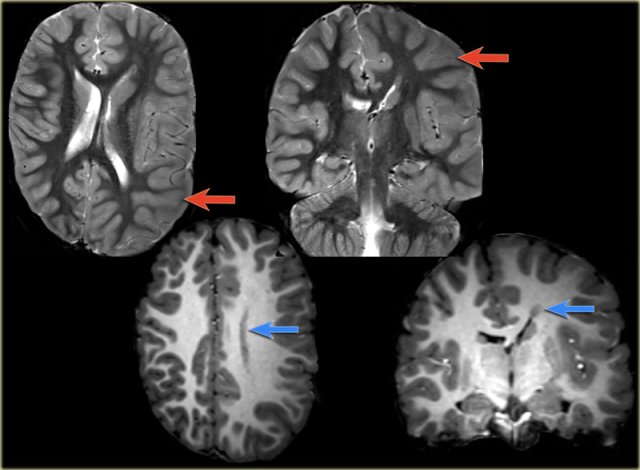

The images show typical focal cortical dysplasia.

There is cortical thickening and blurring of the grey/white matter junction on T1WI (left).

The FLAIR image on the right shows the subcortical hyperintensity.

The images demonstrate cortical and subcortical signal abnormalities on T2WI and FLAIR in the left temporal lobe indicating focal cortical dysplasia.

Notice associated T2/FLAIR hyperintense and shrunken hippocampus as a result of mesial temporal sclerosis, i.e. dual pathology.

Another case of focal cortical dysplasia.

Notice the hypoplastic left temporal lobe with cortical thickening (arrow) and atrophy of the white matter.

Axial T1WI, T2WI and FLAIR-images of a 15 year old boy with epilepsy.

Notice thickening and hyperintensity of the cortex of the left superior frontal gyrus.

The FLAIR-images also show high signal in the subcortical white matter.

These findings are typical for focal cortical dysplasia.